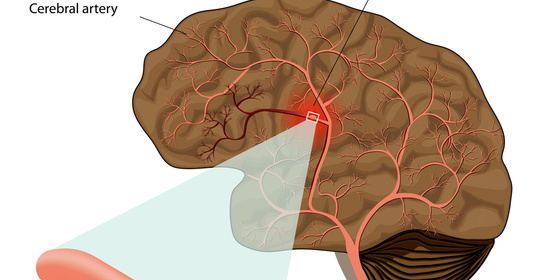

腦實質出血:應對急救和康復的實用指南!